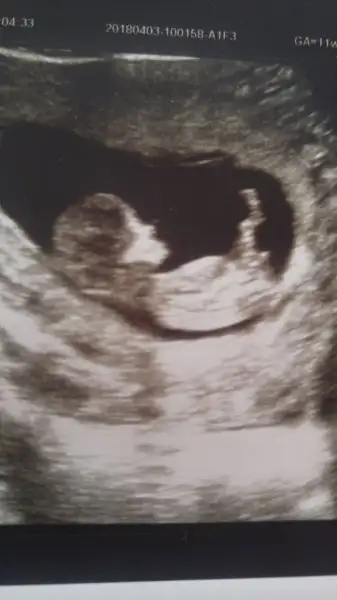

Eki Görüntüle 2153254 Merhaba bayanlar 2 oğlum var 3. Bebiş yolda 8+4 görüntü koyuyorum bana da bir tahmin yapar mısınız

HAYIRLI OLSUNN benım de 8+6 ama burda tahmn yapacak olan yok glb su sıra:) ben hıc anlamıyorum benım kese şeklı fasulye gb eger oyleyse erkek dıyorlar fasulye gb seklı ama kesenın neresınde ya bebiş çözemedim:)